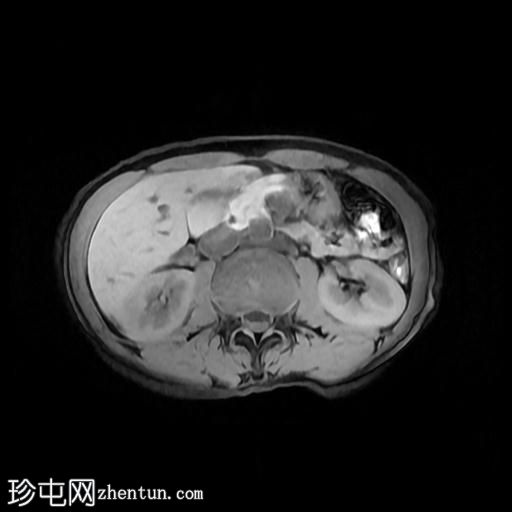

轴位

T2加权像

该宫颈癌体积较大,局部晚期,大小为22 x 40 x 42 mm,起源于宫颈左后外侧壁,向下延伸至阴道上三分之一处,位于宫颈中后外侧壁。

病变还累及左侧前外侧的宫旁组织。

左侧髂内静脉分叉下方可见一异常信号淋巴结肿大,最大短轴直径(SAD)为 8 mm。该淋巴结在弥散加权成像(DWI)上显示水限制,并有对比增强。